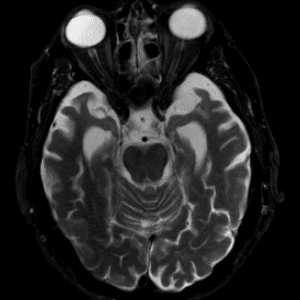

Neurodegenerative Diseases